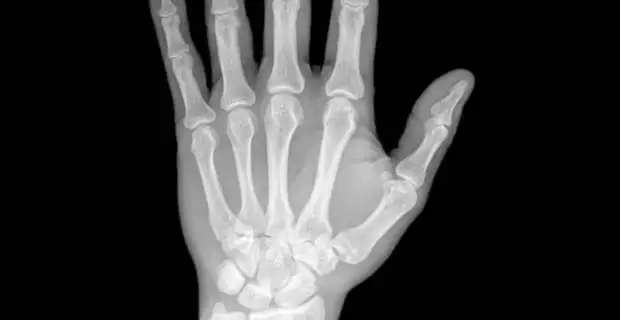

- Manos.

- Muñecas.

- Dedos.

La artritis reumatoide provoca que las articulaciones y los tejidos se inflamen. Por esta razón se dificulta el movimiento normal de todas las articulaciones del cuerpo. Es, además, una enfermedad autoinmune, lo que quiere decir que es el propio organismo que se ataca así mismo por error.

También suelen experimentar un intenso calor, enrojecimiento y deformación de las articulaciones. Además sienten adormecimiento de manos y pies, acompañado de otras enfermedades como el síndrome de ojo seco.